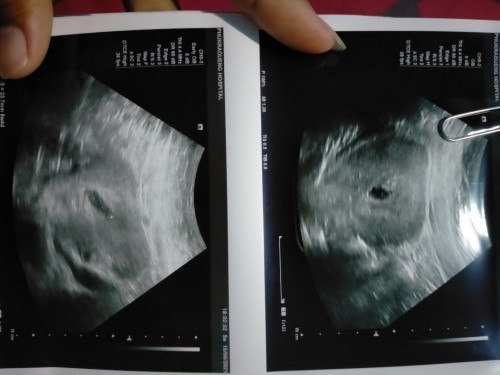

กลัวว่าจะเป็นท้องลม ที่นับจากปะจำเดือนขาดจะ11w6d แต่จากหมอซาวดูให้ได้ 6w4d. แต่หมอสงสัยว่าหน้าจะท้องลม หรือครรอาจจะยังอ่อนอยุ่ แบบนี้จะมีทางเจอตัวอ่อนไหมคะ#ขอคำแนะนำหน่อยค่ะ #ขอบคุณสำหรับคำตอบค่ะ

ของเราก็นับจากปจด.ครั้งสุดท้ายได้12w แต่ไปซาว์ดจริงๆได้6wค่ะ คุณหมอคาดว่า ไข่เราน่าจะตกช้าค่ะ ซาว์ดหน้าท้องเห็นไม่ชัด คุณหมอเลยเปลี่ยนไปซาว์ดช่องคลอด เห็นตัวน้องเล็กมากๆและหัวใจเต้นแล้วค่ะ คุณหมอให้รออีก2อาทิตย์ไปตรวจใหม่ก็ซาว์ดหน้าท้องไม่ค่อยเห็นค่ะ ต้องซาว์ดผ่านช่องคลอดถึงจะเห็น ตัวโตขึ้นเยอะมากและใจเต้นเป็นดิสโก้เลย คุณแม่ ใจเย็นๆ รออีกสัก2อาทิตย์หรือ1เดือนนะคะ น่าจะชัดเจนขึ้นมากค่ะ

อ่านเพิ่มเติมเป็นเหมือนกันเลยค่ะ หมอว่าถ้าท้องลม ถุงใหญ่ปกติแต่ไม่มีตัวเด็กค่ะ หมอนัดซาวน์อีกรอบ วันที่24ค่ะ รอลุ้นเหมือนกัน

ซาวทางช่องคลอดไหมคะแม่ ของเราต้องซาวทางช่องคลอดถึงจะเจอ หมอให้เหตุผลว่าไข่ตกช้า(2w)

น่าจะไข่ตกช้านะคะแม่ อดทนรออีกนิดค่ะ บ้านนี้เจอน้องพร้อมหัวใจเต้น 8 w4d . จ้า

ท้องยังอ่อนมากๆ ตอน9 วีคค่อยตรวจใหม่น่ะ เราเจอตอน9 วิค